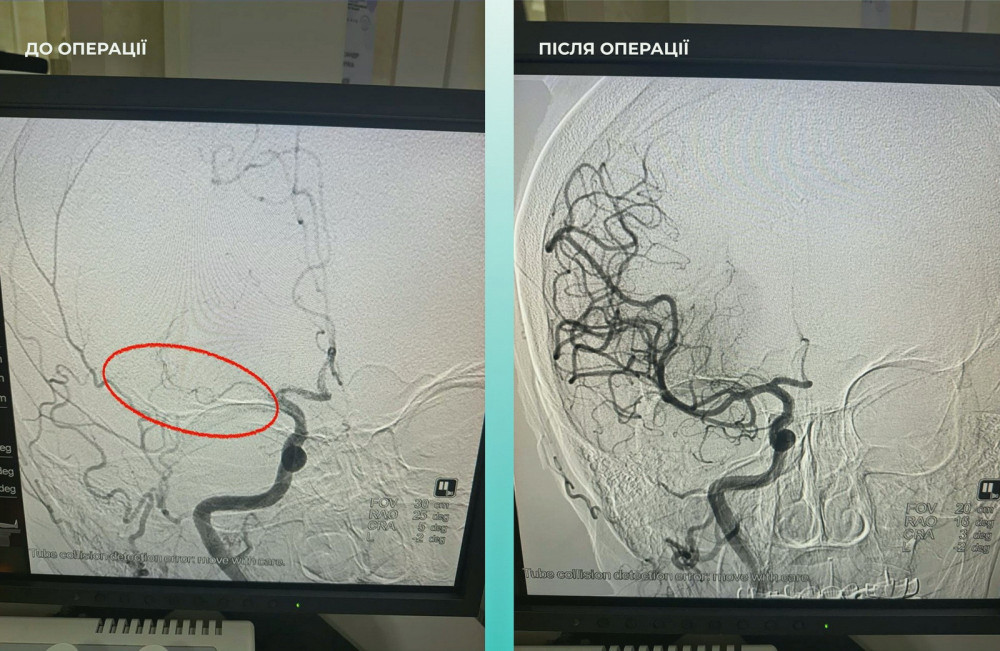

Пациентка поступила в больницу с тяжелым острым инсультом. При проведении компьютерной томографии врачи обнаружили закупорку средней мозговой артерии.

Мультидисциплинарная команда врачей приняла решение провести одновременную тромбоэктомию на мозговых и легочных артериях, что стало критически важным шагом к спасению жизни.